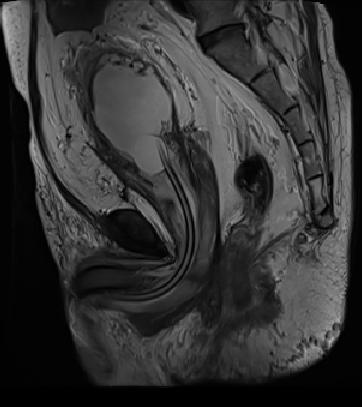

盆腔脂肪增多症是一种原因不明的良性罕见病,是由于大量脂肪堆积于盆腔,包绕压迫膀胱下段、膀胱颈、直肠,使之变形、狭窄,并出现移位,造成膀胱颈部、输尿管下段、乙状结肠、直肠等梗阻改变

特别是泌尿系统症状尤为明显,输尿管逐渐扩张,肾盂积水进行性加重,若病情得不到有效控制,最终可出现肾功能减退,甚至肾功能衰竭